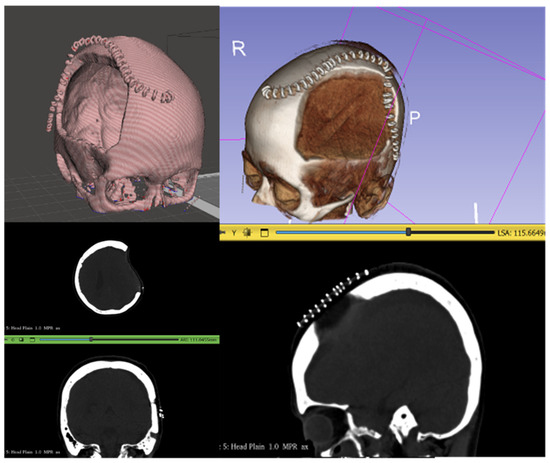

| Misidentification of surgical staples as bone. | Some CT scans included surgical staples overlying the DHC and were detected by CranialRebuild as bone, which impacted the software’s determination of the midsagittal plane. | The recommendation was made to acquire CT scans after staple removal (typically 2 weeks after DHC) but before cranioplasty (2–3 months after DHC). | This specific timing of the CT scan should be recommended in the future use of CranialRebuild 2.0. |